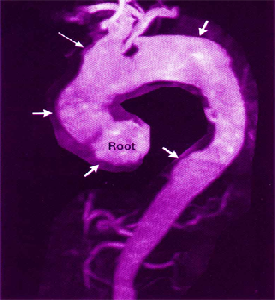

In the play one of Timon’s malignant tirades is directed at two prostitutes. He tells them (Act IV, scene 3, line 153): “…Give them (men) diseases” and …crack the lawyer’s voice, that he may never more false title plead nor sound his quillets shrilly.” It would be a challenge even for modern physicians casually reading the play to interpret these lines. Medical students learn that one of the complications of late stage syphilis is inflammation and weakening of the wall of the large main artery exiting the heart, the ascending aorta. Wrapping normally under this vessel is the left recurrent laryngeal nerve that innervates the left vocal cord. When the ascending aorta expands to the near-

MRI scan showing swollen aorta within the arrows

The neuropathological form of late stage syphilis, known as tabes dorsalis, affects the spinal cord. Only diabetes and tabes dorsalis cause lightning-